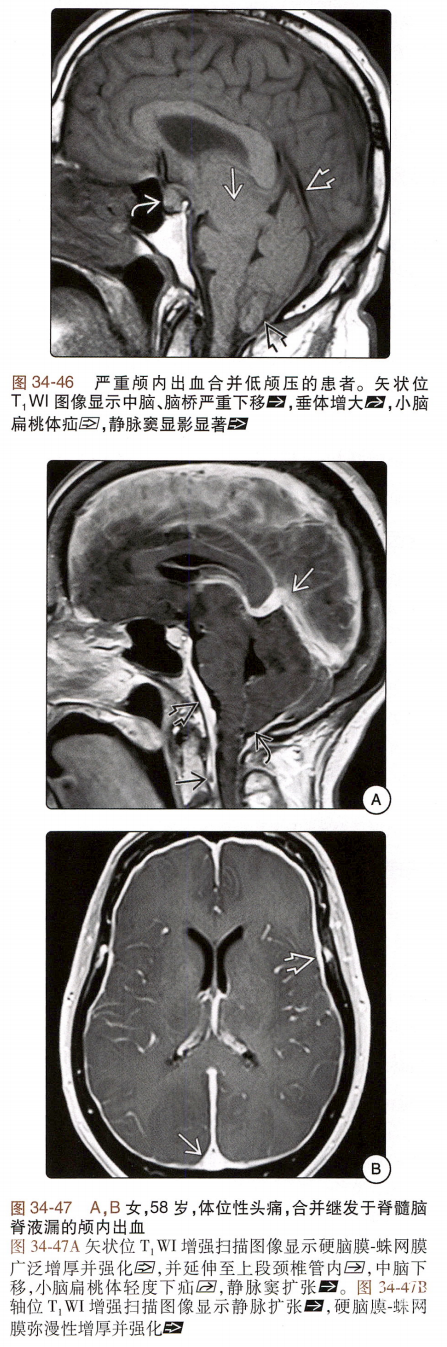

低颅压综合征